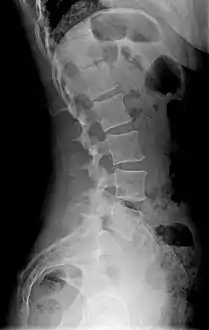

Diagram showing normal curvature (posterior concavity) of the cervical (neck) and lumbar (lower back) vertebral column (spine)